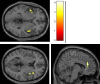

Results: We found very similar patterns of increased BOLD signal to these images in the two groups; both groups showed increased BOLD signal in the bilateral amygdala, as well as in the nucleus accumbens, orbitofrontal cortex, and insula. Direct group comparisons revealed that the ASD group showed a stronger response to food cues in bilateral insula along the anterior-posterior gradient and in the anterior cingulate cortex than the control group, whereas there were no neural reward regions that showed higher activation for controls than for ASD.

Conclusion: These results suggest that neural response to primary rewards is not diminished but in fact shows an aberrant enhancement in children with ASD.